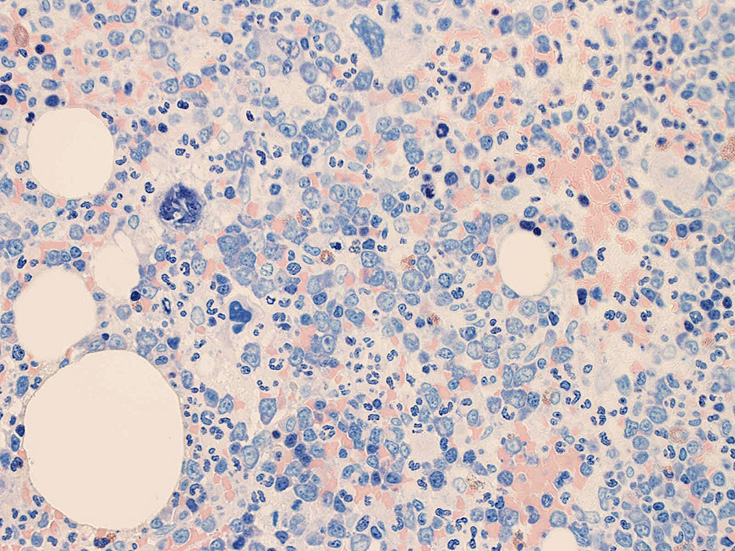

骨髄所見2

異型細胞が集簇, 散在性に増殖している。N/C比大. 粗なクロマチンをもち核小体を複数もつ核に紫の色調の細胞質をもった大型細胞である。類円形の核の他, くびれや捻じれを示す核, 多型な核も出現しているように見える(May-Giemasa染色)。HEでも大型細胞の集族がある. smearの異型細胞は濃い青色調の細胞質にアズール顆粒が認められる。核クロマチンは凝集しているように見える。

骨髄免疫染色およびISH

MG染色での大型異型細胞はCD56, CD30陽性。CD3は陰性を示す